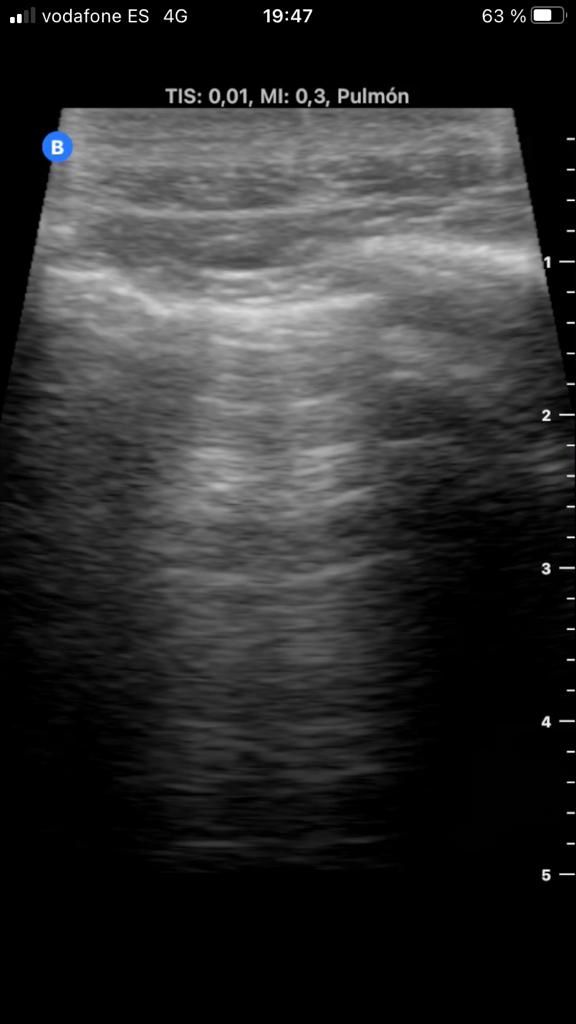

- ECOGRAFIA PLEURAL Y PULMONAR